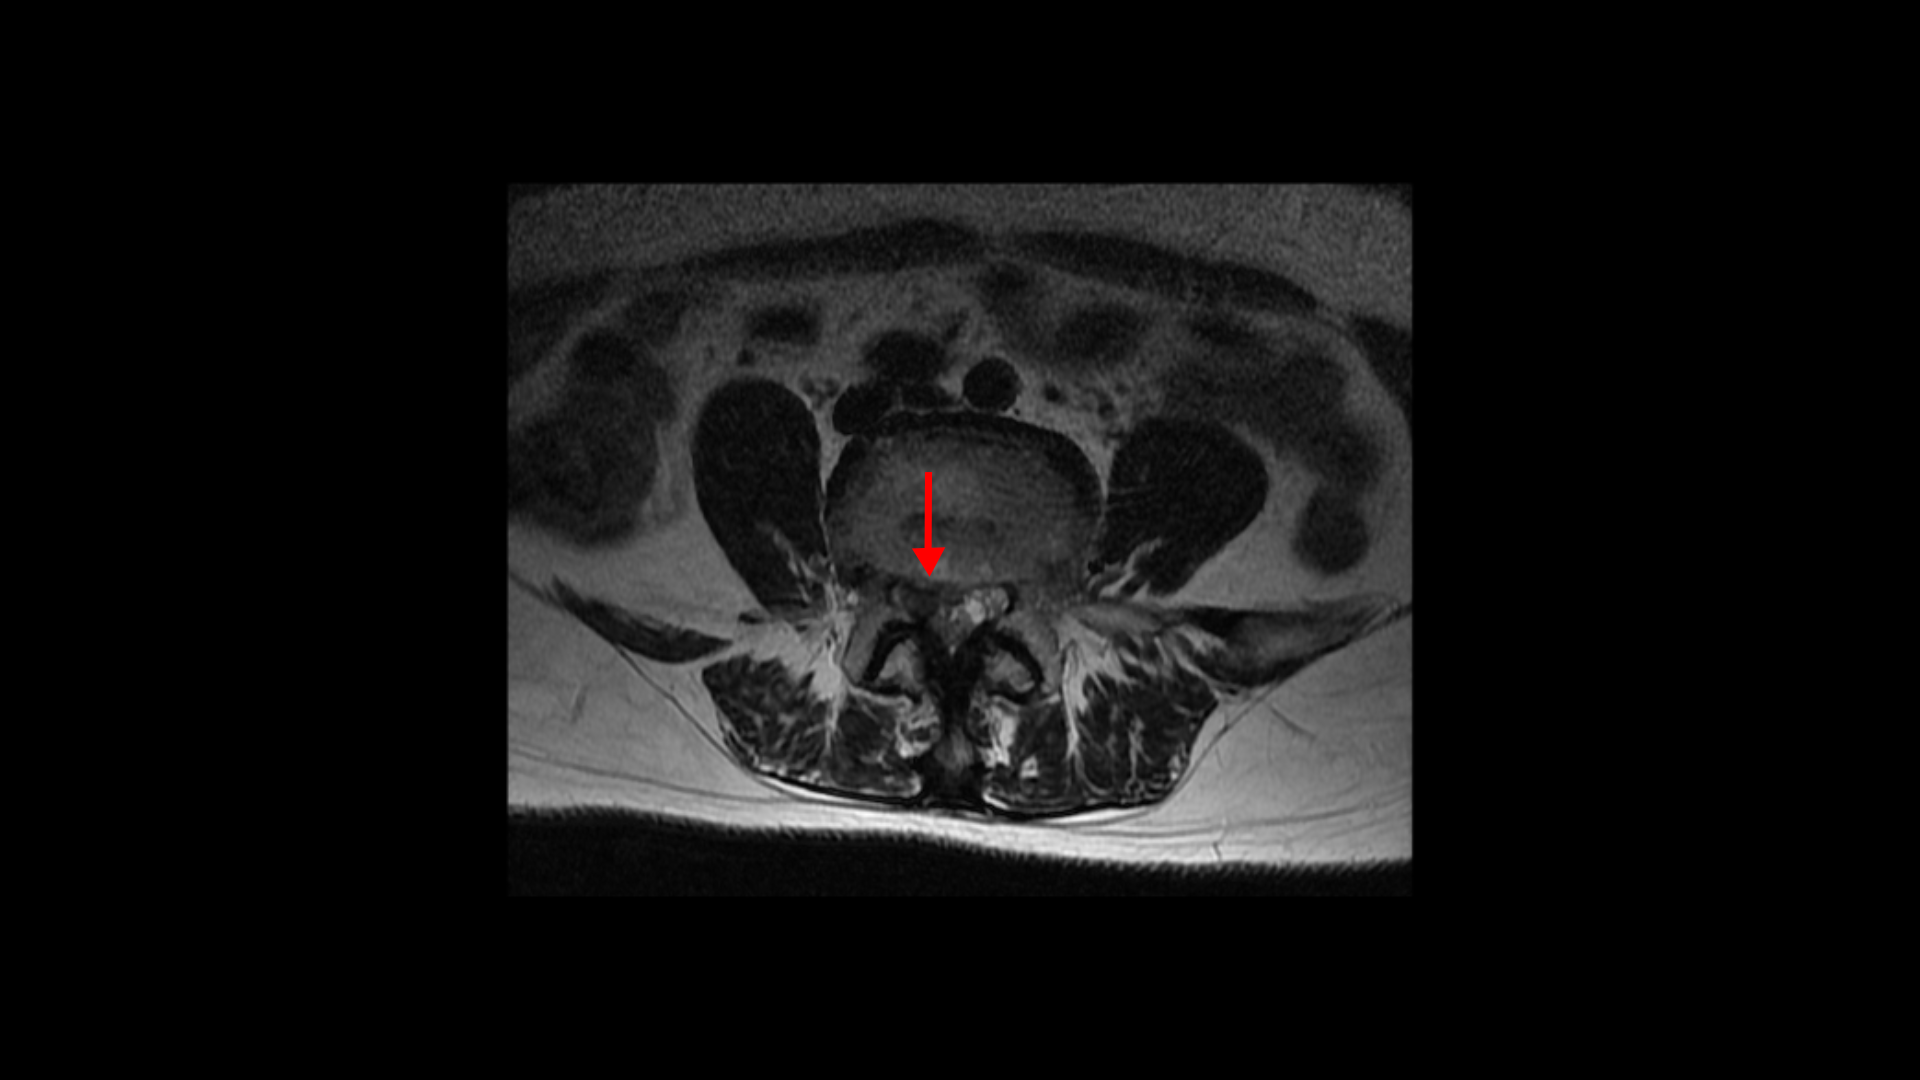

축상면에서 보면 흘러내린 수핵이 신경이 있어야 할 자리를 차지하고 있는 것이 보입니다.

또 보시다시피 이 4번 5번 마디에서는 심한 중심성 협착도 있습니다.